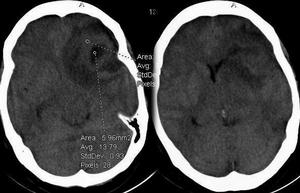

(一)腦動脈硬化症(cerebral arteriosclerosis) 本症多50歲以上發病,